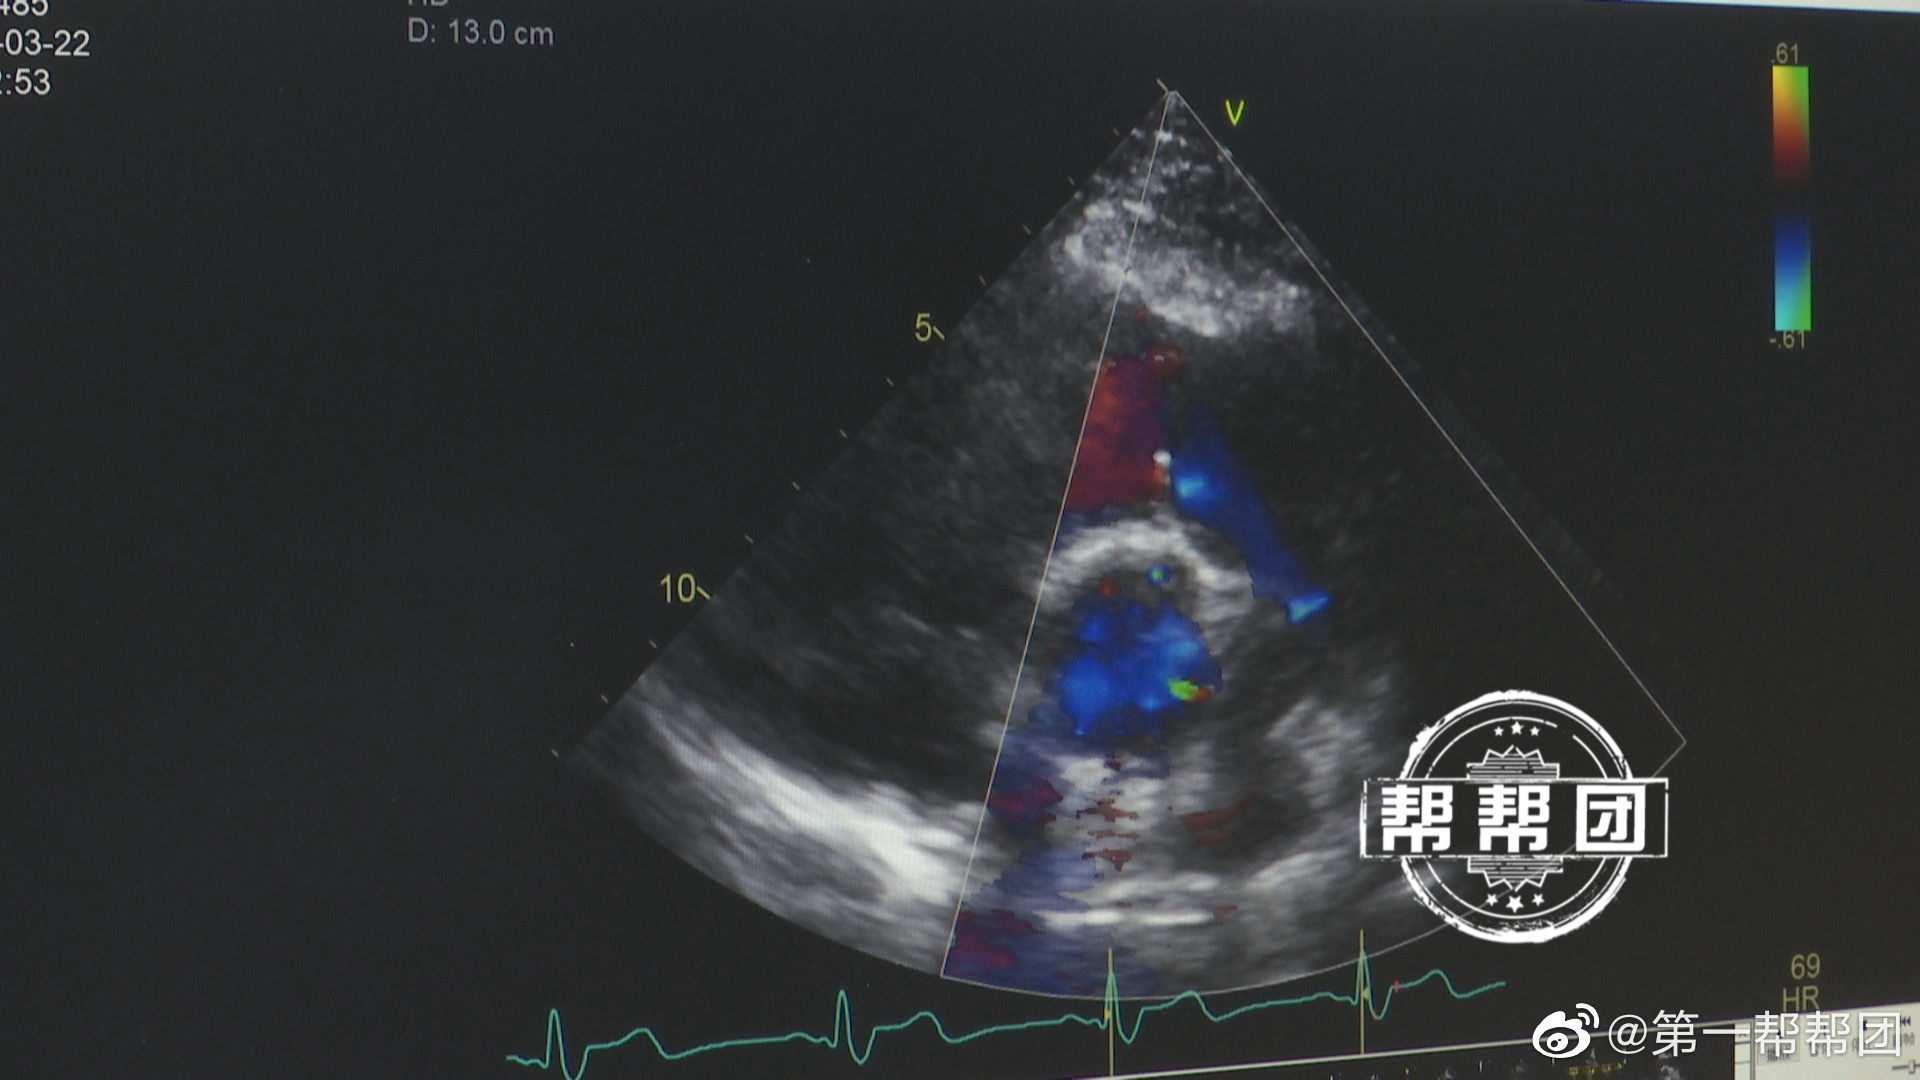

【年轻男子气喘无力,竟是心脏“阀门”松了】#福建首例经导管肺动脉瓣膜置换术成功# 近日,福州一名23岁男子突然出现运动后气促,尤其是在重体力活动或上坡时特别明显,总是感觉乏力。到医院检查后,被诊断为重度肺动脉瓣关闭不全。此病简单说就是心脏肺动脉的一个阀门松了,导致血液倒流,心脏无法正常向全身供血供氧,他的心脏功能因此变得越来越差。于是,福建医科大学附属协和医院心血管内科的医生们利用导管为其进行肺动脉瓣膜置换,最终手术成功。医生介绍,这也是福建首例经导管肺动脉瓣膜置换术。据了解,该男子因先天性心脏缺陷曾经历过一次心脏手术,不过肺动脉里的瓣膜问题没有彻底解决。近期,该男子由于经常熬夜,心脏功能进一步受损,如果没有及时治疗,随时有心衰猝死的风险。医生指出,瓣膜是心脏与大血管上的重要组成结构,瓣膜病在所有心脏问题中占有很大比重。像心脏容量负荷过重、心律失常、年龄、感染,以及高血压、高血脂、高血糖等,都可加重心脏瓣膜病。医生提醒,在日常生活中要注意保持良好的心态,不要有心理负担,保持情绪的稳定;最好不要经常熬夜,养成规律的作息习惯。一旦出现肢体水肿、活动力下降、口唇发紫、气喘气促等症状时,应高度警惕心脏上的瓣膜出了问题,要及时就医。#帮帮团快讯#via@第一帮帮团